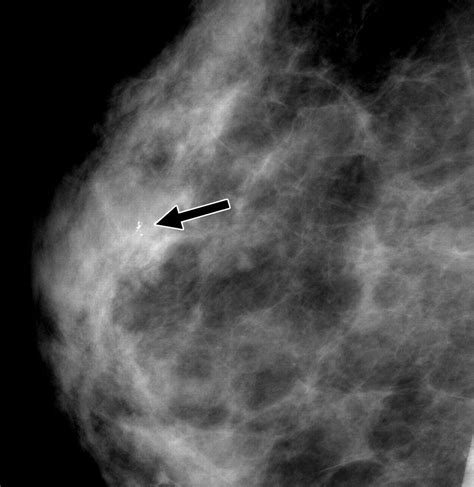

• Imaging Tests: Imaging tests such as mammography, ultrasound, or MRI may be used to visualize the affected tissue and rule out other conditions.